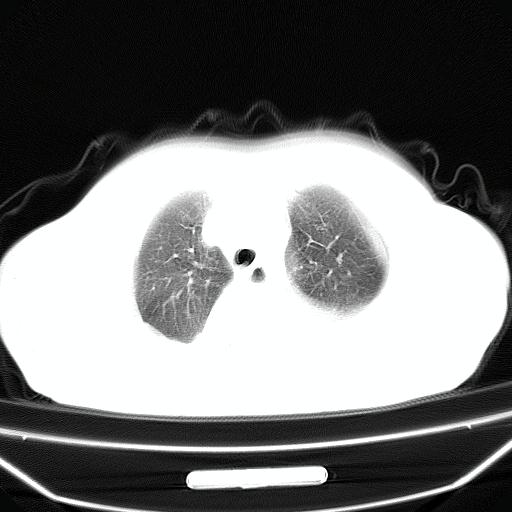

以下是引用lijuanln在2008-4-19 23:05:00的发言:[br]两侧胸腔积液,肺水肿[br]心包积液[br]提示心衰

以下是引用jiangjing在2008-4-20 10:43:00的发言:[br]结合病史支持 冠心病[冠状动脉钙化],心功能不全,肺淤血、肺水肿,双侧胸腔与斜裂积液

以下是引用liuyue在2008-4-19 22:25:00的发言:[br]先考虑:1.心衰伴肺水肿、双侧胸腔积液、叶间积液、双下肺不完全性肺不张; [br] 2.冠状动脉粥样硬化。